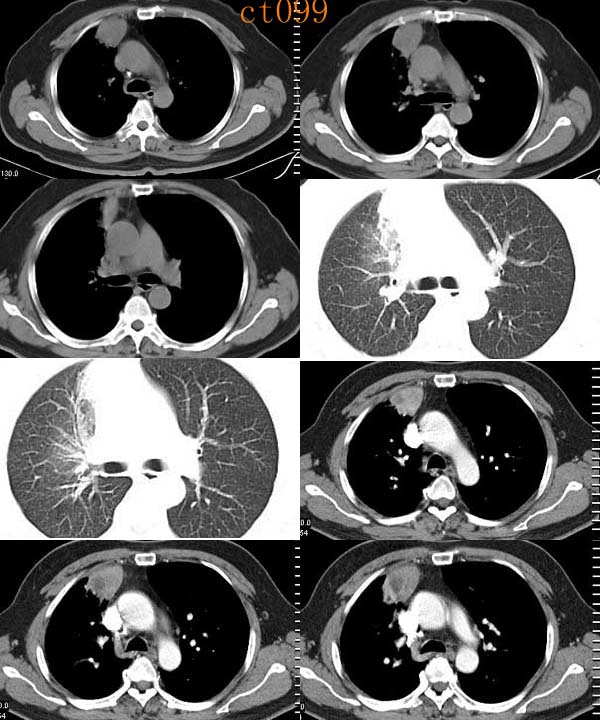

(1)发生部位:炎性假瘤可发生在两肺的任何部位,但多位于肺的表浅部位,邻近胸膜处或者靠近叶间裂。可以跨叶生长,原因可能是跨叶浸润的炎症使得假瘤跨叶融合的结果。

(2)假瘤形态:炎性假瘤的形态不一,可呈圆形.椭圆形或类圆形,也可呈驼峰状或不规则图形。

(3)假瘤大小:多数假瘤的直径在2-4cm,也可大于5cm,少数甚至大于10cm.

(4)假瘤密度:炎性假瘤一般为中等密度,密度均匀。而脓性炎症形成的假瘤则有时可见小空洞。空洞可以单发也可多发。少数瘤体切开时可见脓性物。

(5)假瘤边缘:

①有假无假性包膜者边缘清楚。有的由于肿块不规则可表现分叶状。

② 无假性包膜者,假瘤周围有纤维化和多种细胞成分侵润,表现为片状、边缘模糊的团块状影。或有轻度的渗出性病变,边缘模糊,以组织细胞围增生型多见。有的假瘤周围还可以出现类似周围型肺癌的放射冠状表现。

(6)邻近改变:位于肺周边部的假瘤,其邻近胸膜可见局限性粘连增厚。位于近肺门区的假瘤,偶可阻塞支气管,形成肺叶不张而将假瘤包裹,甚似中央性肺癌,但不出现肺门或纵膈淋巴结肿大。